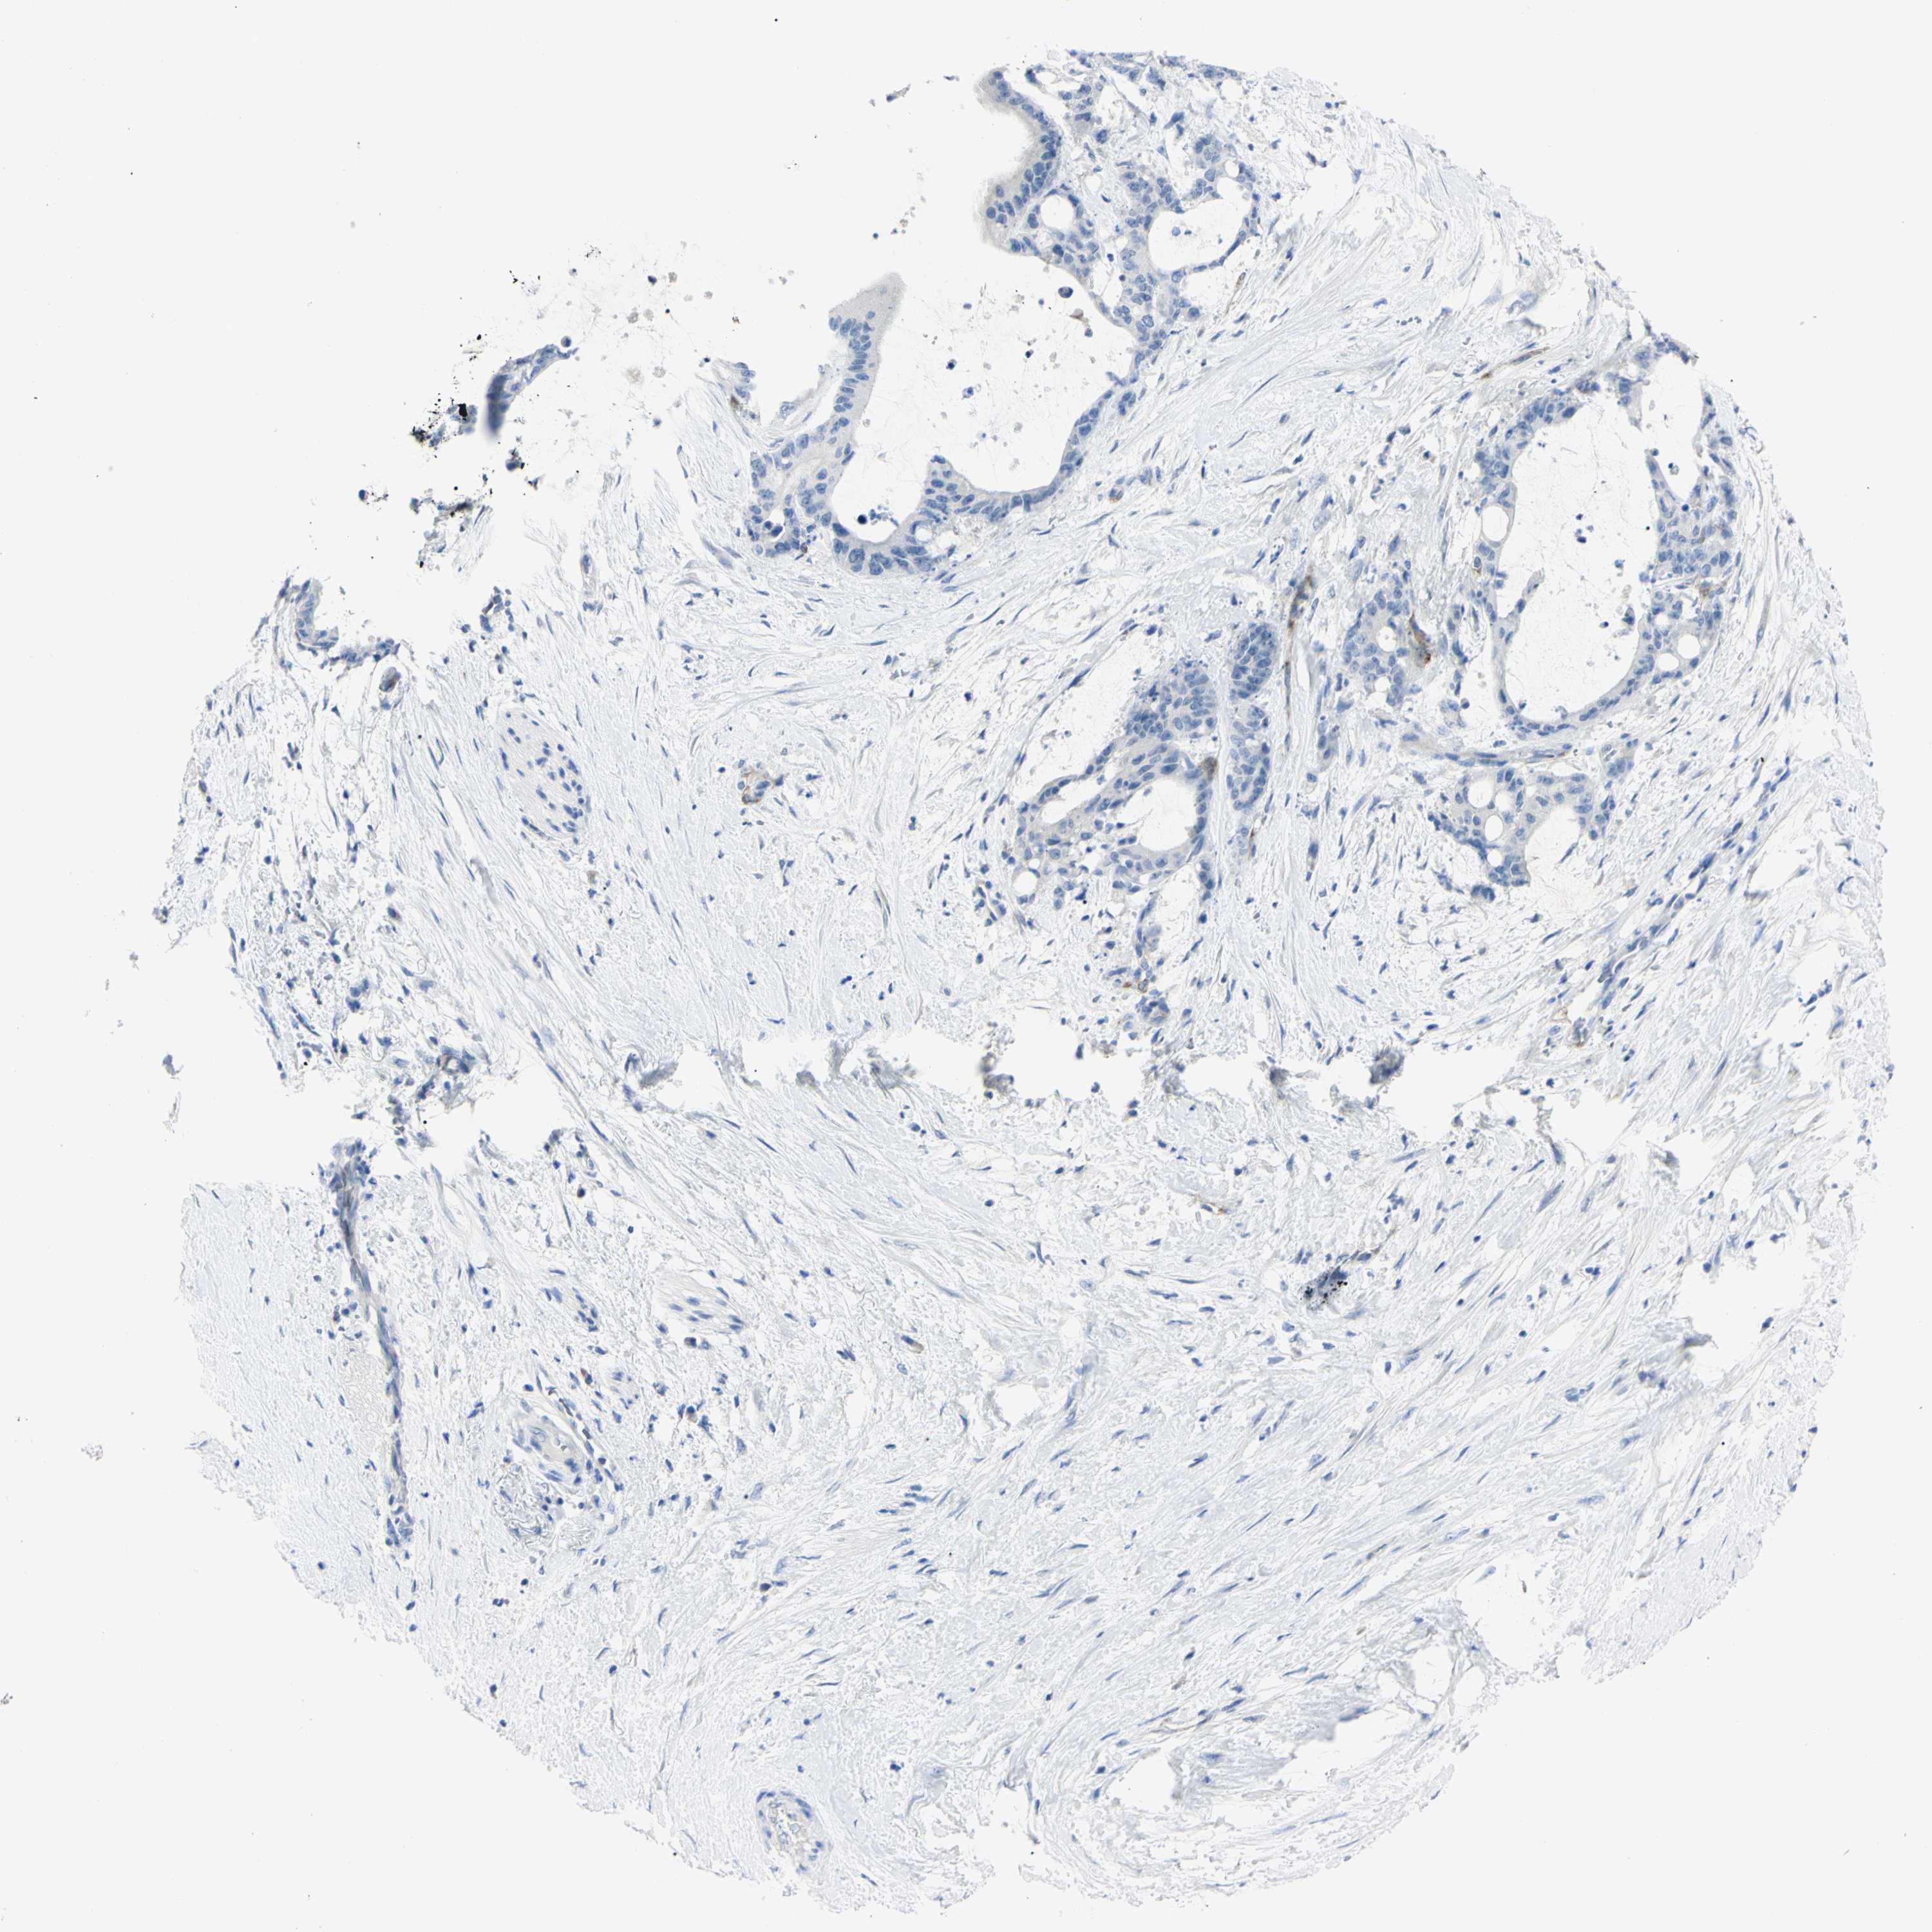

LIVER CANCER - Protein expressioni

A mouse-over function shows sample information and annotation data. Click on an image to view it in a full screen mode. Samples can be filtered based on level of antibody staining by selecting one or several of the following categories: high, medium, low and not detected. The assay and annotation is described here.

Note that samples used for immunohistochemistry by the Human Protein Atlas do not correspond to samples in the TCGA dataset.

Antibody stainingi

Antibody staining in the annotated cell types in the current human tissue is reported as not detected, low, medium, or high, based on conventional immunohistochemistry profiling in selected tissues. This score is based on the combination of the staining intensity and fraction of stained cells.

Each image is clickable and will lead to virtual microscopy that enables deeper exploration of all samples and also displays staining intensity scores, fraction scores and subcellular localization as well as patient and tissue information for each sample.

Antibody HPA010593

Antibody CAB001451

Staining

High

Medium

Low

Not detected

Intensity

Strong

Moderate

Weak

Negative

Quantity

>75%

75%-25%

<25%

None

Location

Nuclear

Cytoplasmic/membranous

Cytoplasmic/membranous,nuclear

Cholangiocarcinoma

Carcinoma, Hepatocellular, NOS